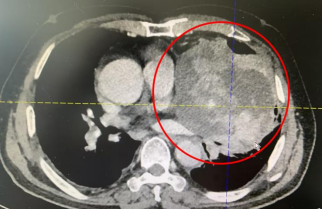

133 mm 的巨大肿瘤

几乎占满左侧胸腔

体积大、侵犯广、牵涉血管神经多

严重压迫心脏、肺动静脉

左上肺被挤到快「消失了」

10 月 9 日,叶惠龙总院长与手术团队紧密协作,凭着高超的技术、细致的操作、扎实的功底、丰富的经验,高度专注,如履薄冰地将肿瘤与周围组织、脏器仔细分离,经过两个多小时,约 133 mmX111 mmX118 mm 大小的肿瘤被完整剥离,手术十分顺利,病理报告 AB 胸腺瘤。